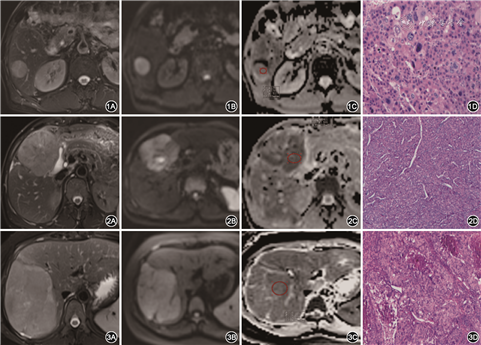

203例HCC患者中,181例Ki67的表达为阳性,占比89%(181/203);60例Ck19的表达为阳性,占比30%(60/203);将Ki67和Ck19的表达与HCC患者的临床病理特征(性别、年龄、肿瘤直径、肿瘤位置、切缘情况、脉管癌栓、AFP、肿瘤分化程度、复发、淋巴结转移、肝内是否转移)进行分析,结果显示Ki67表达阳性、阴性组间HCC脉管癌栓、AFP、肿瘤分化程度、复发、淋巴结转移差异有统计学意义(χ²=5.156、12.741、29.925、3.963、77.408;均P<0.05),其他临床病理特征在Ki67表达阳性、阴性组间差异均无统计学意义(χ²=0.893、0.052、0.586、0.327、0.634、1.049;均P>0.05)。Ck19表达阳性、阴性组间脉管癌栓、AFP、复发、淋巴结转移差异有统计学意义(χ²=9.058、27.034、4.053、14.187;均P<0.05),其他临床病理特征在Ck19表达阳性、阴性组间差异均无统计学意义(χ²=0.234、0.613、0.986、2.120、3.209、0.001、2.787;均P>0.05)(图1, 2, 3)。